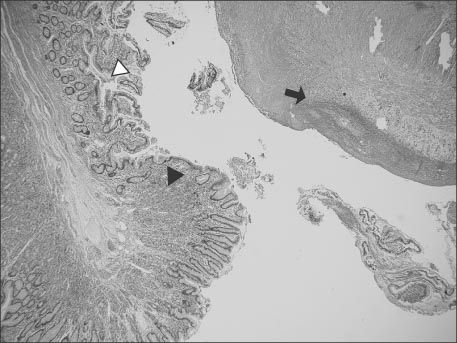

Fig. 2

Abdominal CT shows suspicious intraperitoneal and retroperitoneal abscess with air collection due to suspicious bowel perforation (white arrows).

We considered this patient as bacterial enteritis and started symptomatic treatment. On the 3rd hospital day, the patient suddenly showed massive bloody stool. His vital signs were as follows: blood pressure, 95/70 mmHg; heart rate, 93 beats/min; respiratory rate, 21 breaths/min; and temperature, 39.5℃. Physical examination on abdomen showed rigidity, voluntary guarding and tenderness on palpation in the entire abdominal area. Bowel sounds were decreased. Laboratory data were as follows: sodium, 140 mEq/L; potassium, 3.3 mEq/L; chloride, 102 mEq/L; BUN/creatinine, 2.7/0.32 mg/dL; CRP, 118 mg/dL; and glucose, 93 mg/dL. The CBC was as follows: WBC, 15,420/µL; neutrophils, 69.4%; Hb/Hct, 8.9/26.6%; and platelets, 346,000/µL. Abdominal CT showed suspicious intraperitoneal and retroperitoneal abscess with air collection due to possible bowel perforation (Fig. 2).

Fig. 2 Abdominal CT shows suspicious intraperitoneal and retroperitoneal abscess with air collection due to suspicious bowel perforation (white arrows).